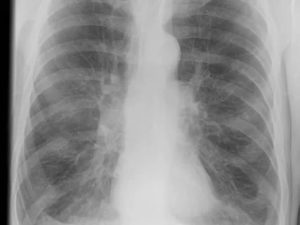

Рассмотрим для примера рентгеновский снимок легких в норме:

На нем визуализируется множество затемнений и просветлений (белого и черного цвета), которые могут запугать читателей. На самом деле эта рентгенограмма расшифровывается просто (см. следующий снимок)

На рентгенограмме подписаны все анатомические структуры, чтобы читателям было легко разобраться. Предлагаем запомнить интенсивность легочных полей. Норма не предполагает наличия патологических затемнений (белого цвета) и просветлений (темного цвета), которых нет на изображении.

Рентген здоровых легких описывать следует по классическому стандарту. Вначале вносятся записи о патологических рентгеновских синдромах, затем легочные поля, корни, купола диафрагмы, реберно-диафрагмальные синусы, сердечная тень и мягкие ткани.

Классический алгоритм описания здоровых легких:

- В легочных полях без видимых очаговых и инфильтративных теней;

- Корни не расширены, структурны;

- Контуры диафрагмы и реберно-диафрагмальные синусы без особенностей;

- Сердечная тень обычной конфигурации;

- Мягкие ткани без особенностей.

Вышеприведенная рентгенограмма подпадает под данное описание.